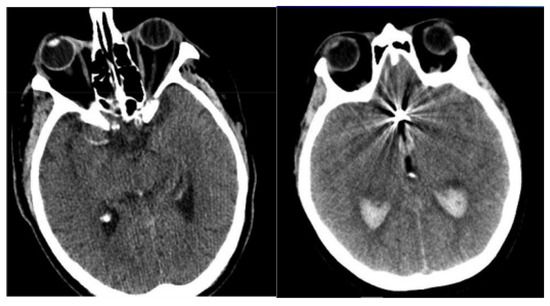

- Finally, determine the differences in orientation and intensity of the pixels and using Equations (3) and (4). The sample-segmented images are graphically presented in Figure 3, where the red area denotes the segmented portions.

Figure 3. Sample-segmented images.

The process of segmentation using modified region-growing is important, because it mainly impacts the capacity of feature extraction and classification because the poor segmentation causes noise or irrelevant details which affect classification. A precise segmentation separated the hemorrhagic regions from the images and confirmed that only appropriate areas were transferred to feature extraction. This helped in extracting the significant features that lead to the enhancement of the capacity of classifying the SAH grade. After performing the segmentation, the isolated portions were given as input to the feature extraction where the pre-trained models were utilized to extract appropriate features.